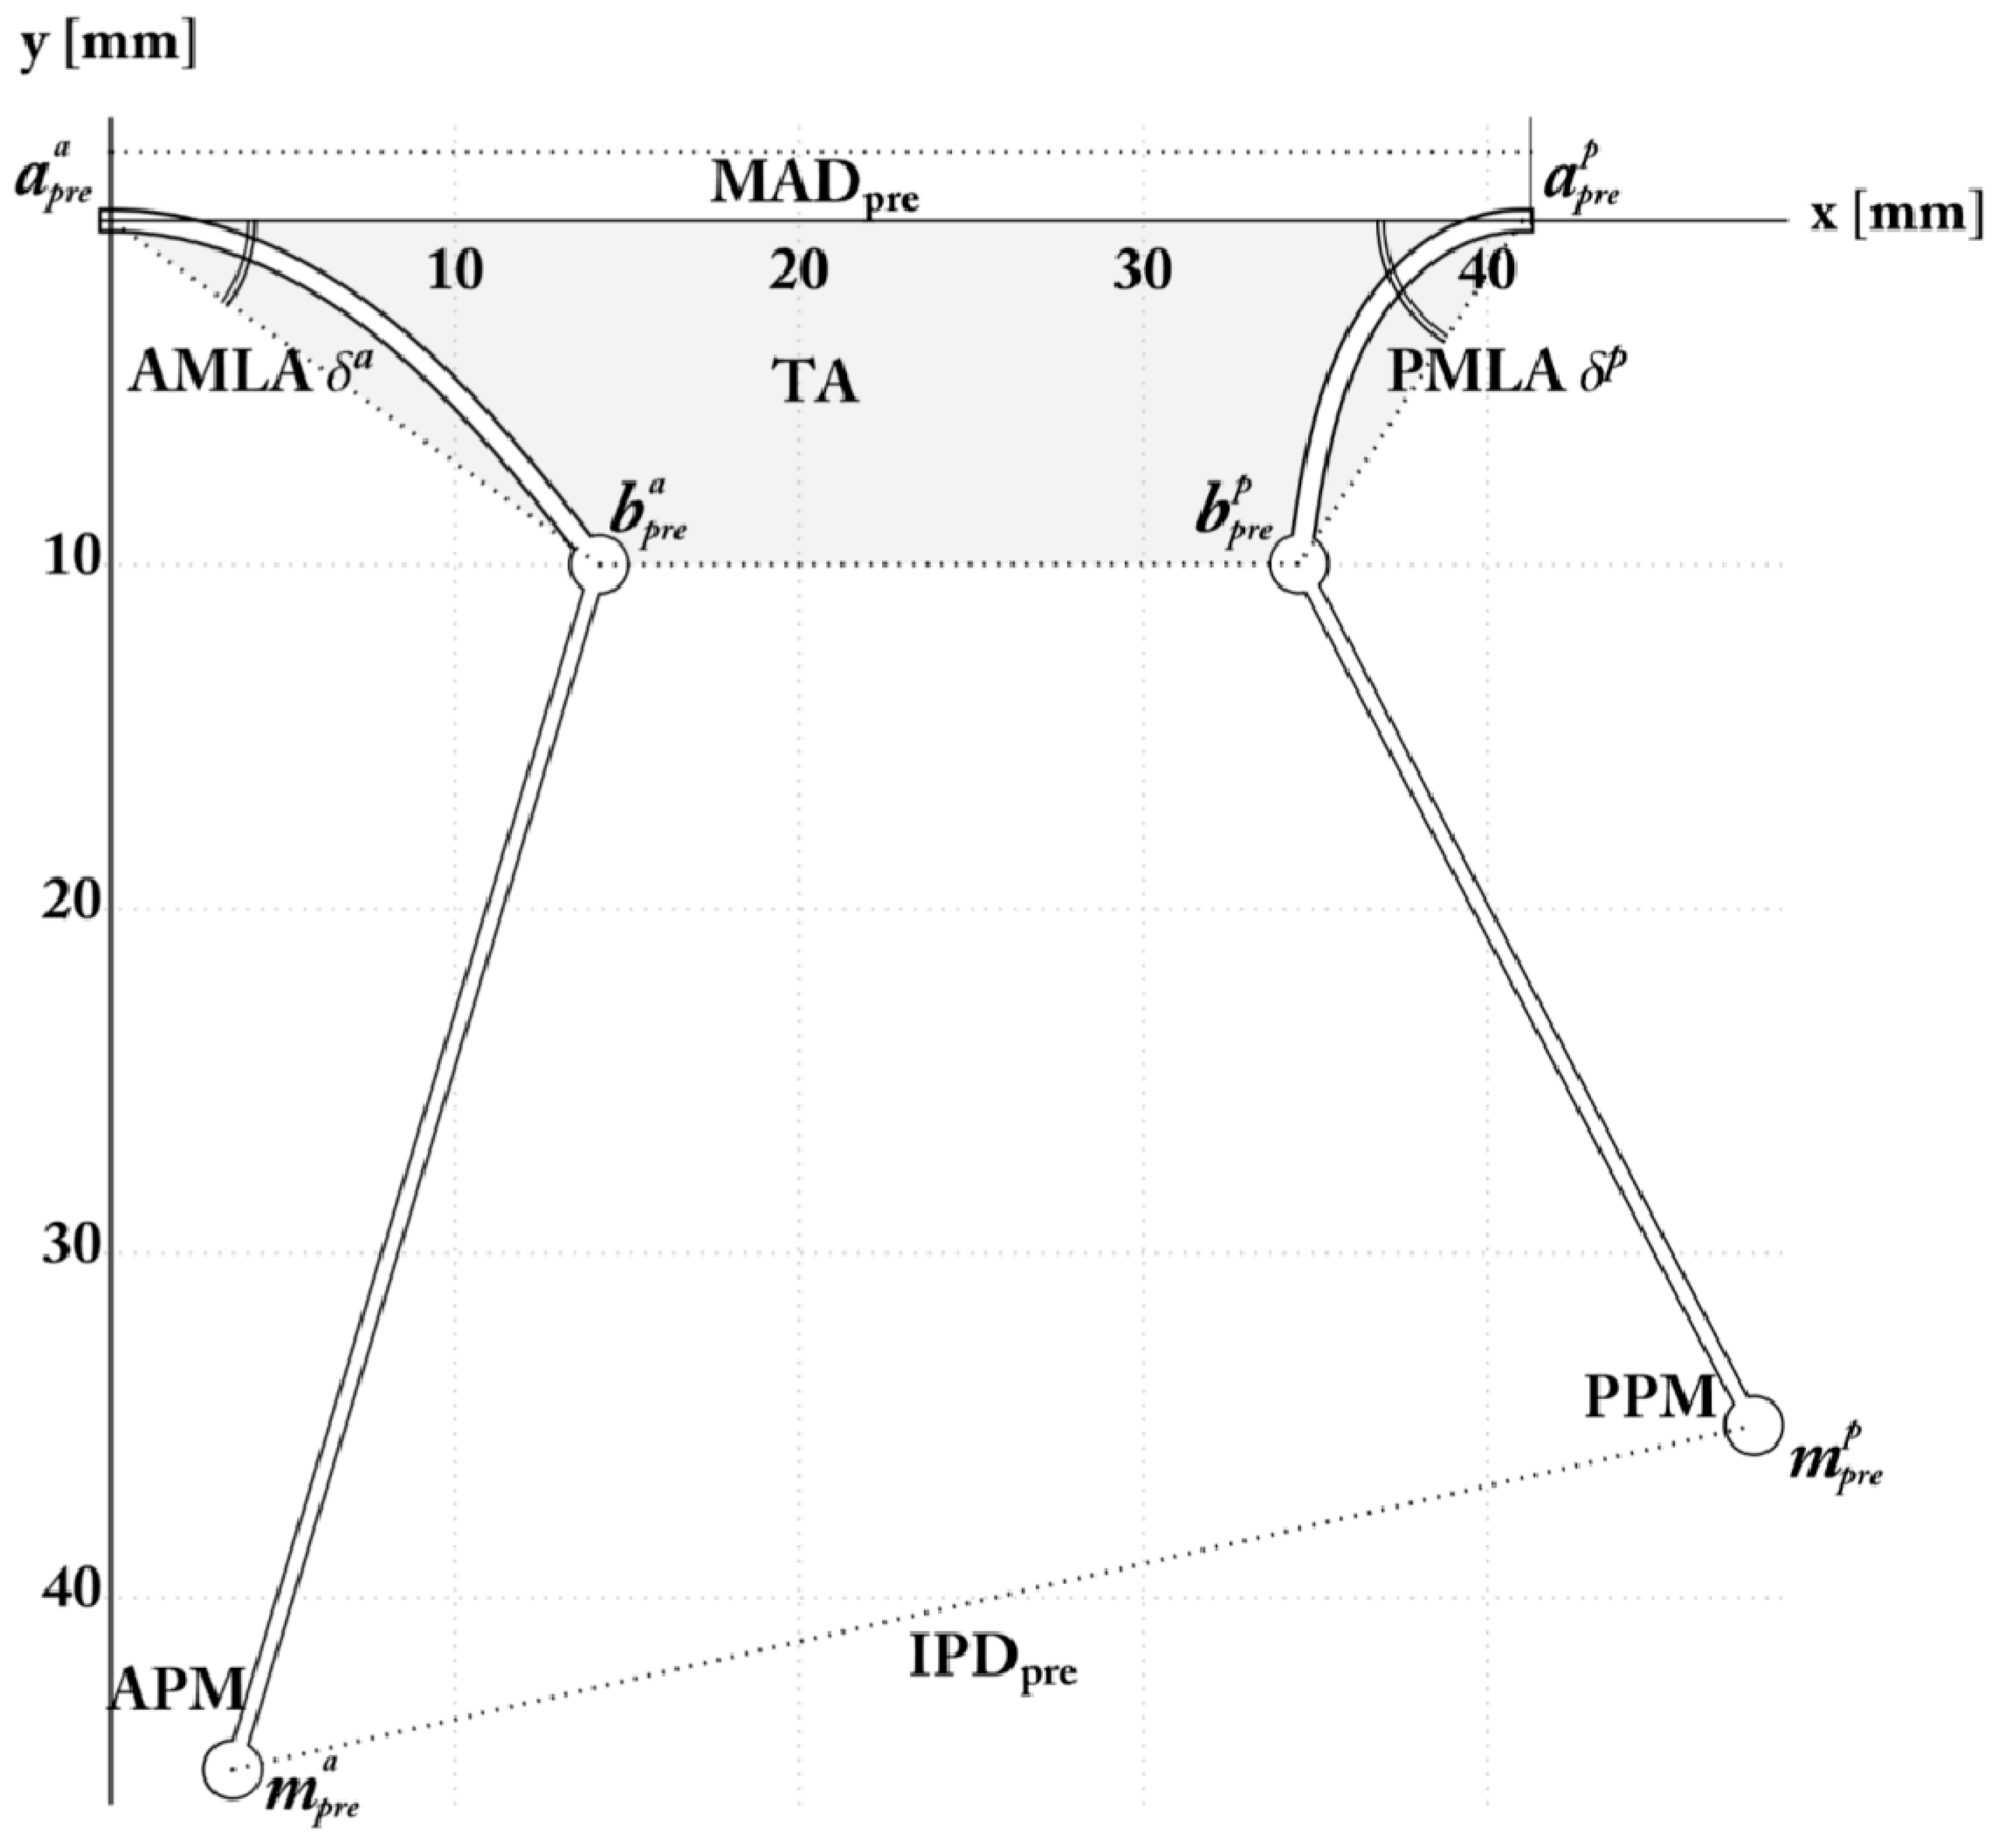

The Pre-Operative Configuration

3.1. Mitral Valve: Annulus and Leaflet

3.2. Mitral Valve: Subvalvular Apparatus